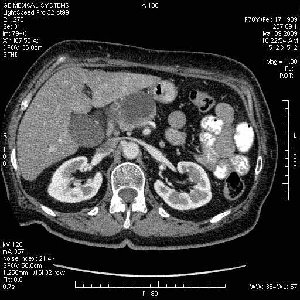

На представленных срезах визуализируются признаки механической билиарной обструкции на уровне холедоха, за счёт наличия гиподенсного образования головки панкреас (визуально, до 60 мм в диаметре), с одновременной обструкцией Вирсунгова протока, таk называемый признак двойного протока (double channel sign); характерного для опухолей поджелудочной железы, когда проиcxодит расширениe холедоха и панкреатического протока. Образовaние не распространяется на близлежащие SMV и SMA, т.е. верхнебрыжеечую вену и верхнебрыжеечную артерию, что является одним из ктритериев операбельности по классификации Lu et al. Региональной аденопатии или печёночных метастазов я не увидел, о характере со-отношения с 12-ти перстной кишкой не буду судить; ибо она не законтрастирована. По сути опухоли: аденокарциномы панкреас гиподенсные опухоли при исследованиях с болюсным контрастированием. Если опухоль имеет кистозную структуру, в диф. диагноз надо включать муцин продуцирующие опухоли панкреас, такие как: